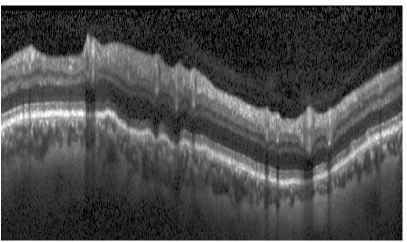

Average boundary-wise results are summarized in Table 2. In general, boundaries 1 and 6 to 9 turned out to be easier to segment than boundaries 2 to 5. For boundary 1 this stems from easily detectable textures, whereas boundaries 6-9 with their regular shape profit disproportionately from regularization by the shape prior. Boundaries 2-5 on the other hand pose a harder challenge with their high variability of texture and shape. The upper row in Fig. 9 shows an example close to the average segmentation performance with Eunsgn=2.97μmsubscript𝐸unsgn2.97𝜇𝑚E_{\mathrm{unsgn}}=2.97\,\mu m.

Refer to caption

(a)

(b)

(c)

(d)

Figure 9: Top: Segmentation (Eunsgn=2.97μmsubscript𝐸unsgn2.97𝜇𝑚E_{\mathrm{unsgn}}=2.97\,\mu m) of a non-pathological circular scan. Bottom: Segmentation (Eunsgn=5.09μmsubscript𝐸unsgn5.09𝜇𝑚E_{\mathrm{unsgn}}=5.09\,\mu m) of an advanced glaucomatous scan.

For the pathological scans segmentation performance was comparable to the healthy scans, but decreased with the progression of the disease. This happened for two reasons: Since glaucoma is known to cause a thinning of the nerve fiber layer (NFL) Schuman et al. (1995); Bowd et al. (2001), the shape prior trained on healthy scans may encounter difficulties adapting to very abnormal glaucomatous shapes. Furthermore, we observed a reduced scan quality for glaucomatous scans, also reported by others Ishikawa et al. (2005); Stein et al. (2006); Mayer et al. (2010), which in turn reduced the quality of the data terms. For advanced primary open-angle glaucoma, the NFL can even vanish at some locations. The appearance model for this layer, trained on healthy data, is not able to detect these extreme anomalies, which resulted in a comparatively low performance for some scans. We discuss possible modifications to overcome this problem in Section 7.

The bottom panels in Fig. 9 show an example of a PGA-type scan and its segmentation. The scan exhibits the discussed reduced scan quality. Furthermore, the segmentation proves that the shape model can generalize well to pathological shapes as well as scan artifacts.